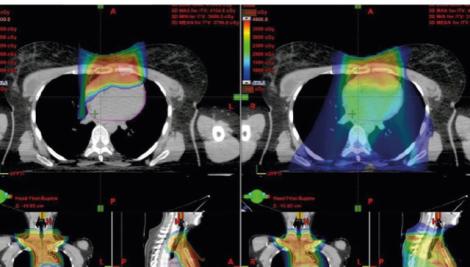

Case Study: Breast

Future Clinical Opportunity: Adaptive Therapy

Future Clinical Opportunity: ConformalFLASH

Future Clinical Opportunity: DynamicARC